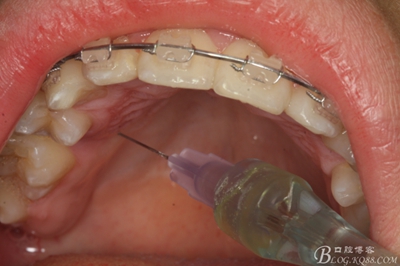

圖5.涂布表面麻醉劑

圖6.唇側(cè)局部無痛浸潤麻醉

圖7.腭側(cè)無痛浸潤麻醉